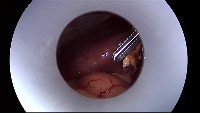

Laparoscopy Computer Vision Project

Surgical Training and Education: Utilizing the "Laparoscopy" computer vision model in surgical simulation tools and training materials to assist medical students and professionals in understanding the intricacies of a laparoscopic gallbladder surgery.

Real-time Assistance in Laparoscopic Surgeries: Using the "Laparoscopy" model to provide real-time feedback and visual information guidance for surgeons during gallbladder removal surgery. This would help in minimizing the risk of complications and increasing the efficiency of the procedure.

Enhanced Post-Surgery Analysis: Analyzing recordings of laparoscopic surgeries with the "Laparoscopy" model to retrospectively identify areas for improvement, document surgical outcomes, and gather data for future training or research purposes.

Pre-Surgical Planning: Employing the "Laparoscopy" model on pre-operative imaging data to identify vital structures and assist surgeons in formulating a personalized surgical plan, reducing potential complications during the procedure.

Development of Robotic-Assisted Surgical Systems: Integrating the "Laparoscopy" computer vision model in the development of autonomous or semi-autonomous robotic surgery systems, enabling them to accurately identify and interact with essential components during gallbladder-related laparoscopic procedures.